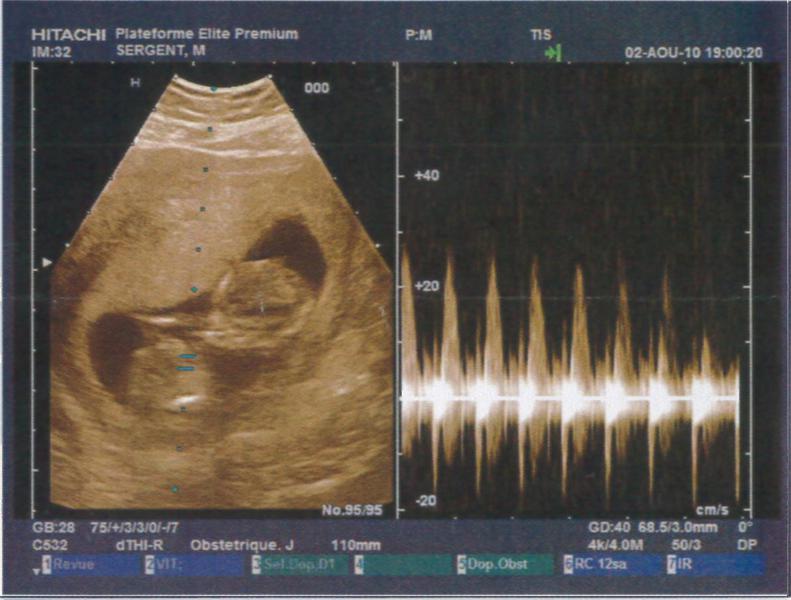

Je suis à 12SA soit 10SG, j'ai fait mon écho hier soir et tout va super bien !!! Je suis trop heureuse je vais vraiment pouvoir vivre ma grossesse à fond !! La nuque est parfaite, à vérifier par le test de la trisomie la semaine pro en même temps que la déclaration !!

Je vous met les photos des échos mais je trouve que l'on ne voit rien par rapport aux superbes images que nous avons vues !! Mais c'est pas grave, on a un super souvenir quand même !!

Pièces jointes

• echo1.jpg

echo1.jpg

53.6 KB · Affichages: 70

• echo2.jpg

echo2.jpg

53.8 KB · Affichages: 68

• echo3.jpg

echo3.jpg

52.7 KB · Affichages: 69

• echo4.jpg

echo4.jpg

55.4 KB · Affichages: 70

• echo5.jpg

echo5.jpg

50.7 KB · Affichages: 71